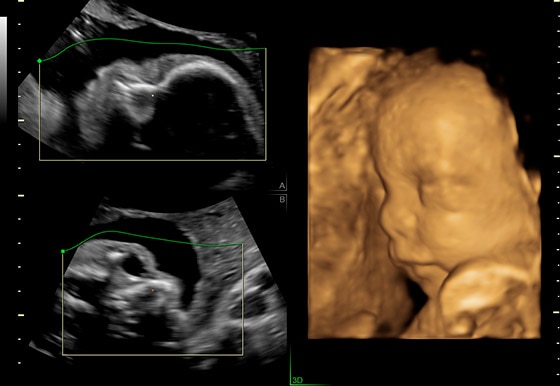

УЗИ аппарат Voluson P8 (серии Performance) создан для решения ежедневных задач. С ним ультразвуковое исследование становится абсолютно простым и доступным методом диагностики, помогающим принимать в акушерской и гинекологической практике важные клинические решения.

- Получение превосходных 2D-изображений без усилий.

- Дополнительные плоскости сканирования при 3D-исследованиях для детальной оценки анатомических структур.

- Отличные 2D-изображения — с оптимальными настройками для максимальной четкости и детализации.

Простота получения 3D-изображений

Визуализация в режимах 3D/4D позволяет исследовать дополнительные анатомические плоскости, повышая вашу уверенность в диагностике.

- Визуализация плоскостей недоступных для исследования при 2D-сканировании, для более точной диагностики.

- Точная постановка диагноза благодаря экспертным 3D/4D-технологиям Voluson.

3D-технологии Voluson позволяют получить дополнительные плоскости визуализации, недоступные при рутинном сканировании в 2D.